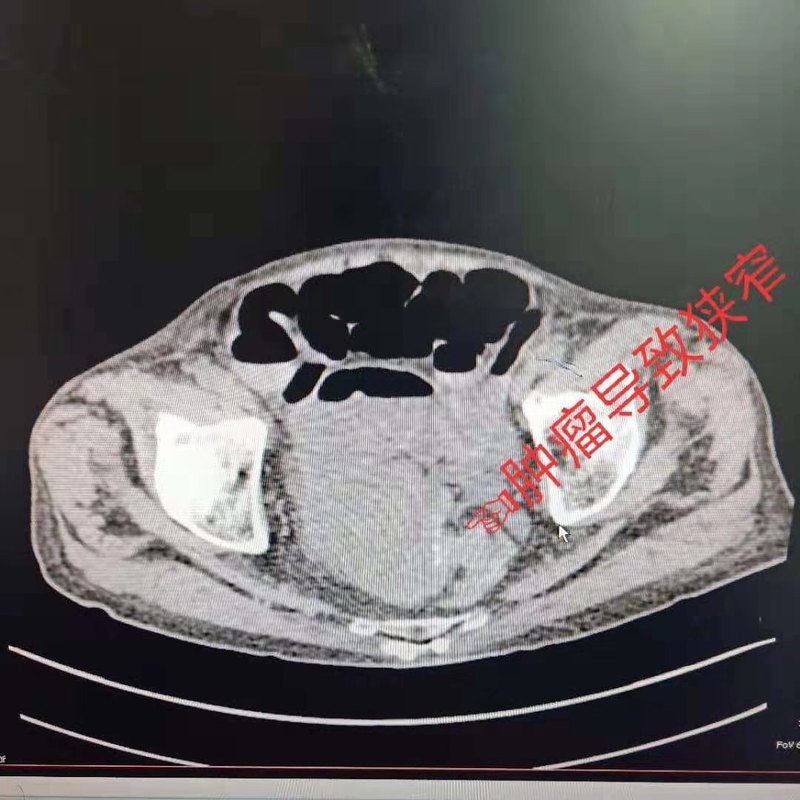

高齡合并急性結(jié)腸癌性腸梗阻,一直是困繞大家的難題,許多醫(yī)生和患者家屬都感到棘手,不敢做決擇,很多患者可能最終被迫行了造口術(shù),或者放棄了手術(shù),但是在我處,我們有針對性的選擇不同的方法處理,都是微創(chuàng)手術(shù)。最終都恢復非常好。上圖是一位91歲老年患者,因高齡,腸癌擔心手術(shù),在多家醫(yī)院不接后轉(zhuǎn)來我院,在我的帶領(lǐng)下,輕松解決問題。術(shù)后9天輕松出院。我在胃,結(jié)直腸癌治療方面有獨到見解,有豐富的臨床經(jīng)驗,在湖南省各地區(qū)會診并傳授微創(chuàng)技術(shù)